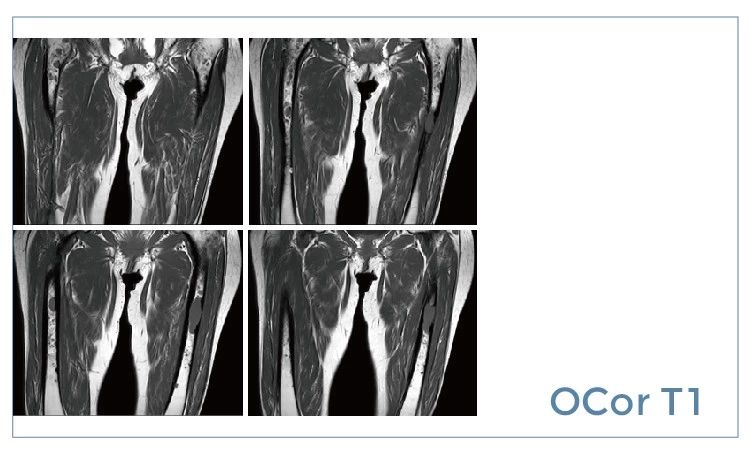

【朗润影像档案】20190802磁共振影像病例结果讨论

【朗润影像档案】磁共振影像病例分享(编号20190802)